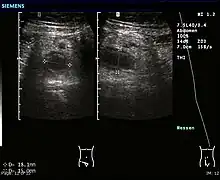

Ultrasound

Abdominal ultrasonography, preferably with doppler sonography, is useful to detect appendicitis, especially in children. Ultrasound can show the free fluid collection in the right iliac fossa, along with a visible appendix with increased blood flow when using color Doppler, and noncompressibility of the appendix, as it is essentially walled-off abscess. Other secondary sonographic signs of acute appendicitis include the presence of echogenic mesenteric fat surrounding the appendix and the acoustic shadowing of an appendicolith.[55] In some cases (approximately 5%),[56] ultrasonography of the iliac fossa does not reveal any abnormalities despite the presence of appendicitis. This false-negative finding is especially true of early appendicitis before the appendix has become significantly distended. Also, false-negative findings are more common in adults where larger amounts of fat and bowel gas make visualizing the appendix technically difficult. Despite these limitations, sonographic imaging with experienced hands can often distinguish between appendicitis and other diseases with similar symptoms. Some of these conditions include inflammation of lymph nodes near the appendix or pain originating from other pelvic organs such as the ovaries or Fallopian tubes. Ultrasounds may be either done by the radiology department or by the emergency physician.[57]